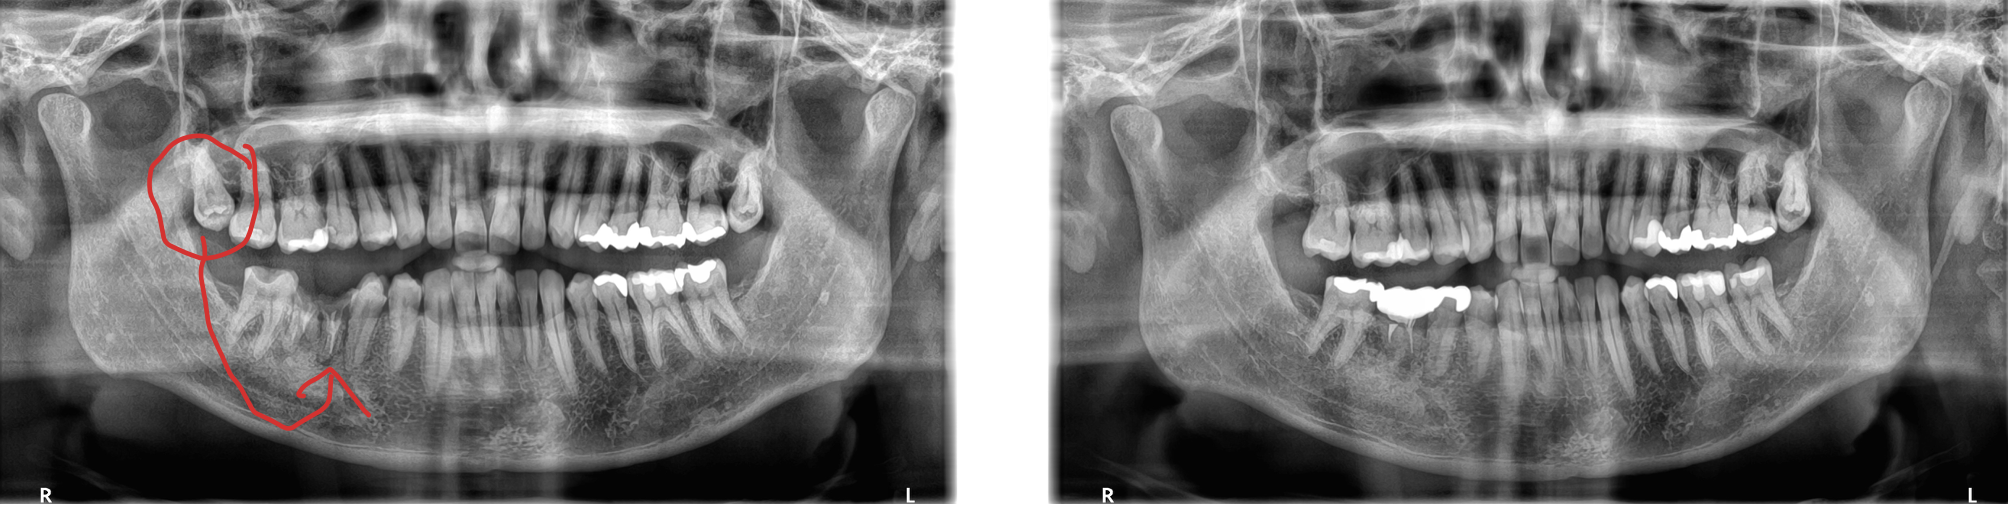

右上の親知らずを右下に移植した症例 保険適用内 歯の根のサイズが合えば適用可能